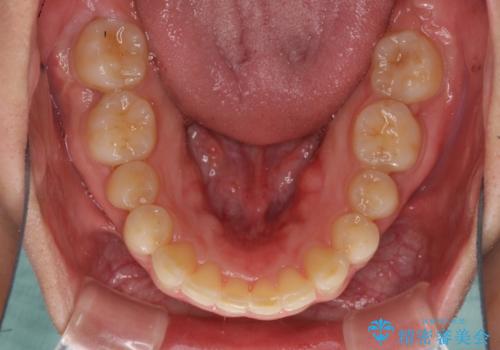

矯正治療とインプラント治療を同じ歯科医師が担当することで、通常見られるような複数医院を行き来する煩雑さや、複数担当医の見解の違いによる治療の遅滞といった煩わしさは一切なく、スムーズに治療を進めることができました。

安定して咬めるようになり、患者様には大変満足していただきました。